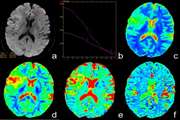

A meeting at the Radiology Research Center of Tehran University of Medical Sciences was held with IT manager Dr. Rezaei to address the center’s IT infrastructure needs. Key topics included improving medical imaging systems (PACS), hospital information systems (HIS), and data storage for AI. Future sessions are planned to collaborate with hospital radiology departments to resolve these challenges.